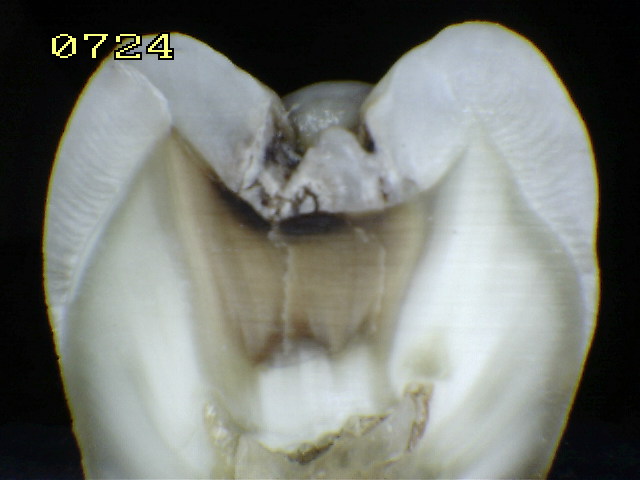

Espécimen Nº 62 |

Corte sagital en fosal mesial "A" y

distal "B" |

Código histológico 2 en "A" |

Código histológico 1 en "B" |